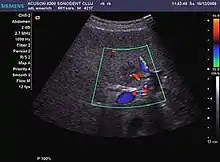

The ultrasound appearance is a well defined lesion, with very thin, almost unapparent walls, without circulatory signal at Doppler or CEUS investigation. The content is transonic suggesting fluid composition. The presence of membranes, abundant sediment or cysts inside is suggestive for parasitic, hydatid nature. Posterior from the lesion the acoustic enhancement phenomenon is seen, which strengthens the suspicion of fluid mass. They typically displace normal liver vessels but no vascular or biliary invasion occurs.

Hemangioma

It is the most common liver tumor with a prevalence of 0.4 – 7.4%. It is generally asymptomatic but also can be associated with pain complaints or cytopenia and/or anemia when it is very bulky. It is unique or paucilocular. It can be associated with other types of benign liver tumors. Characteristic 2D ultrasound appearance is that of a very well defined lesion, with sizes of 2–3 cm or less, showing increased echogenity and, when located in contact with the diaphragm, a "mirror image" phenomenon can be seen. When palpating the liver with the transducer the hemangioma is compressible sending reverberations backwards. Doppler exploration reveals no circulatory signal due to very slow flow speed. CEUS investigation has real diagnosis value due to the typical behavior of progressive CA enhancement of the tumor from the periphery towards the center. The enhancement is slow, during several minutes, depending on the size of hemangioma and on the presence (or absence) of internal thrombosis. During late (sinusoidal) phase, if totally "filled" with CA, hemangioma appears isoechoic to the liver. Deviations from the above described behavior can occur in arterialized hemangiomas or those containing arterio-venous shunts. In these cases, differentiation from a malignant tumor is difficult and requires other imaging procedures, follow up and measurements of the tumor at short time intervals.[4]